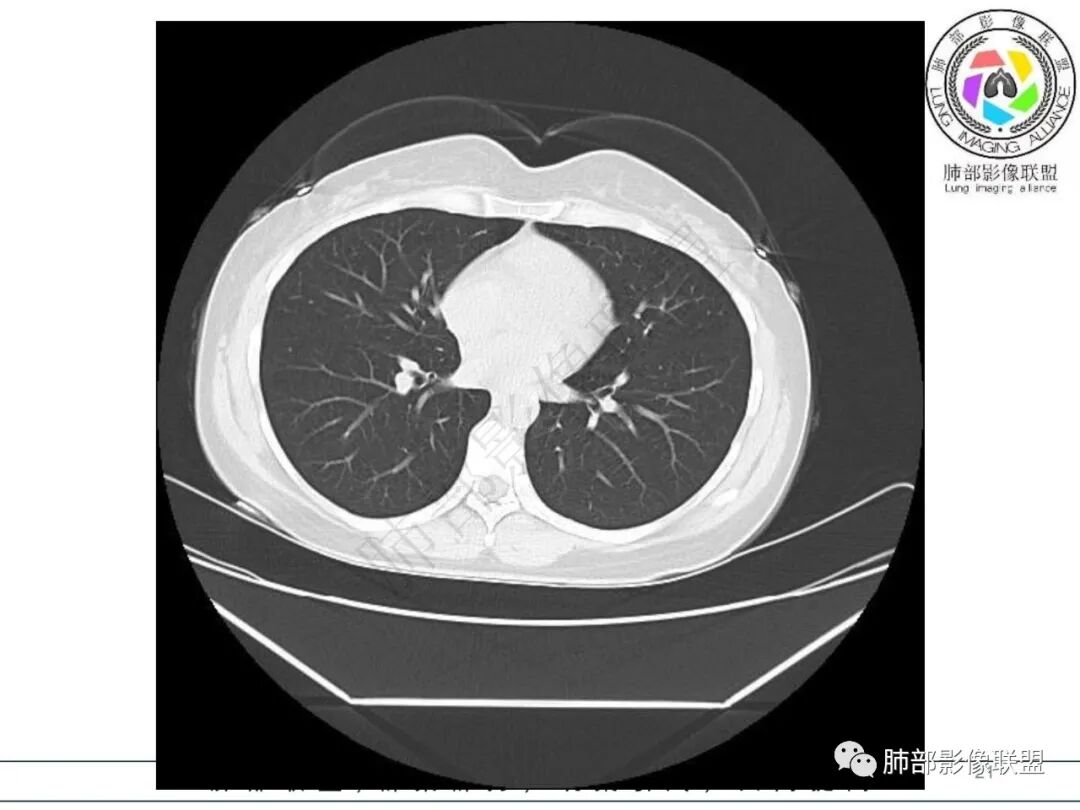

右肺下叶局限性实变影伴晕征。

后、外基底段实变

周围GGO边界不清

内部支气管还算通畅

偏密实区支气管显示欠佳,密度稍低区支气管显示,密实区边缘稍膨隆

2.影像特征:右肺下叶局限性实变影伴晕征,边界不清,内部支气管尚通畅,实变区密实区边缘稍膨隆。符合炎性病灶特征。